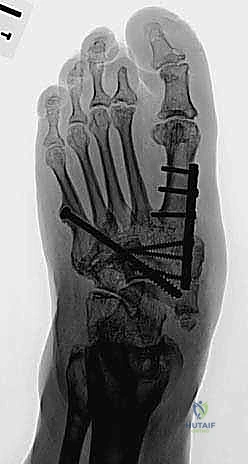

الخطوة الرابعة: إعادة بناء وتثبيت المفاصل (Arthrodesis)

هذه هي المرحلة الأهم، حيث يتم دمج العظام المتضررة معاً لتكوين كتلة عظمية صلبة ومستقرة. يعتمد الدكتور هطيف على تقنيتين رئيسيتين حسب حالة المريض:

أ) التثبيت الداخلي الشديد (Superconstruct Internal Fixation):

استخدام صفائح معدنية سميكة جداً ومسامير طويلة (أقوى من تلك المستخدمة في الكسور العادية) لتثبيت العظام الهشة. يتم وضع هذه الدعامات داخل القدم لتكوين هيكل جديد.